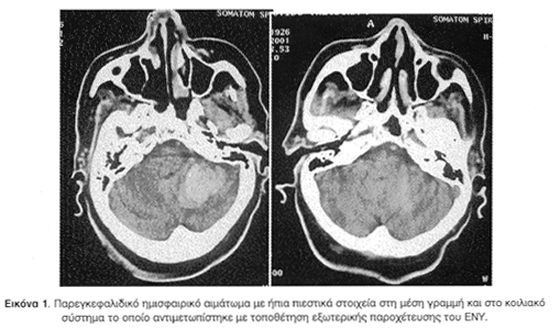

Εννιά (9) περιστατικά αντιμετωπίστηκαν χειρουργικά (6 άμεσα, 3 όψιμα), ενώ τα υπόλοιπα έντεκα ακολούθησαν συντηρητική αγωγή. Οι κυριότεροι παράγοντες που λήφθηκαν υπόψη για την επιλογή του τρόπου θεραπείας ήταν η ηλικία των ασθενών, η αρχική κλίμακα Γλασκώβης (GCS), η ανάπτυξη ή όχι αποφρακτικού υδροκεφάλου και το μέγεθος του αιματώματος. Χειρουργικά αντιμετωπίστηκαν ασθενείς με GCS <13, ημισφαιρικά παρεγκεφαλιδικά αιματώματα με διάμετρο >30x40 χιλ., αιματώματα στο σκώληκα >25x35 χιλ, και αιμορραγίες που προκαλούσαν αποφρακτικό υδροκέφαλο.

Όπως φαίνεται και στο σχετικό πίνακα η πλειονότητα των περιπτώσεων ήταν αιμορραγίες που αφορούσαν στα παρεγκεφαλιδικά ημισφαίρια (14, 70%). Αρχική αποκλειστική εντόπιση στο σκώληκα απαντήθηκε σε τέσσερα (4) περιστατικά (20%), ενώ μικτή εντόπιση δηλαδή και στα ημισφαίρια και στο σκώληκα της παρεγκεφαλίδας παρατηρήθηκε μόνο σε δύο (2) ασθενείς (10%) (Πίνακας 1).

Η αναζήτηση της κατάστασης της κυκλοφορίας του ΕΝΥ και των κοιλιών είναι αποφασιστικός παράγοντας για την πορεία των ασθενών αυτών. Σημειώνεται ότι στα αιματώματα του οπίσθιου βόθρου μπορεί να προκληθεί υδροκέφαλος ευκολότερα από ότι στις υπερσκηνιδιακές αιμορραγίες και να χρειαστεί άμεσα τοποθέτηση παροχετευτικού συστήματος του ΕΝΥ. Σε κάποιες σειρές η ανάπτυξη υδροκεφάλου φαινόταν ότι ήταν ο σημαντικότερος παράγοντας επηρεασμού της έκβασης, απετέλεσε ισχυρή ένδειξη για μια χειρουργική παρέμβαση και συνδέθηκε με πτωχή πρόγνωση. Σε περίπτωση που αποφασιστεί μια χειρουργική επέμβαση η τοποθέτηση παροχετευτικού συστήματος του ΕΝΥ θα πρέπει να αποτελεί πάγια τακτική17,21,22,28,30,32,38.

Έχει κατά καιρούς ειπωθεί ότι σε κάποιους ασθενείς η τοποθέτηση συστήματος παροχέτευσης του ΕΝΥ δεν επαρκεί από μόνη της για να βελτιώσει την κατάσταση και να αποσυμφορήσει τα πιεστικά φαινόμενα στο εγκεφαλικό στέλεχος. Περιπτώσεις παρεγκεφαλιδικών αιματωμάτων οι οποίες αρχικά αντιμετωπίζονται με τοποθέτηση εξωτερικής παροχέτευσης ενδεχομένως αργότερα να χρειαστούν κρανιεκτομία και αφαίρεση της βλάβης, χωρίς αυτό να σημαίνει απαραίτητα ότι θα υπάρξει κλινική βελτίωση. Τα παραπάνω ενισχύουν την άποψη ότι είναι επιτακτική η ανάγκη θέσπισης της κατάλληλης και έγκαιρης θεραπευτικής αντιμετώπισης προτού εγκατασταθούν μη αναστρέψιμες νευρολογικές βλάβες19,32.